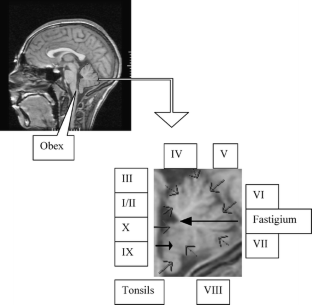

A midsagittal brain MRI slice was selected from each of 68 participants with CII (mean age 13 years). Control participants were 28 typically developing children (mean age 14.1 years). Midsagittal surface areas occupied by the intracranial fossa, posterior fossa, vermis, and its lobules were measured.

Fig. 2